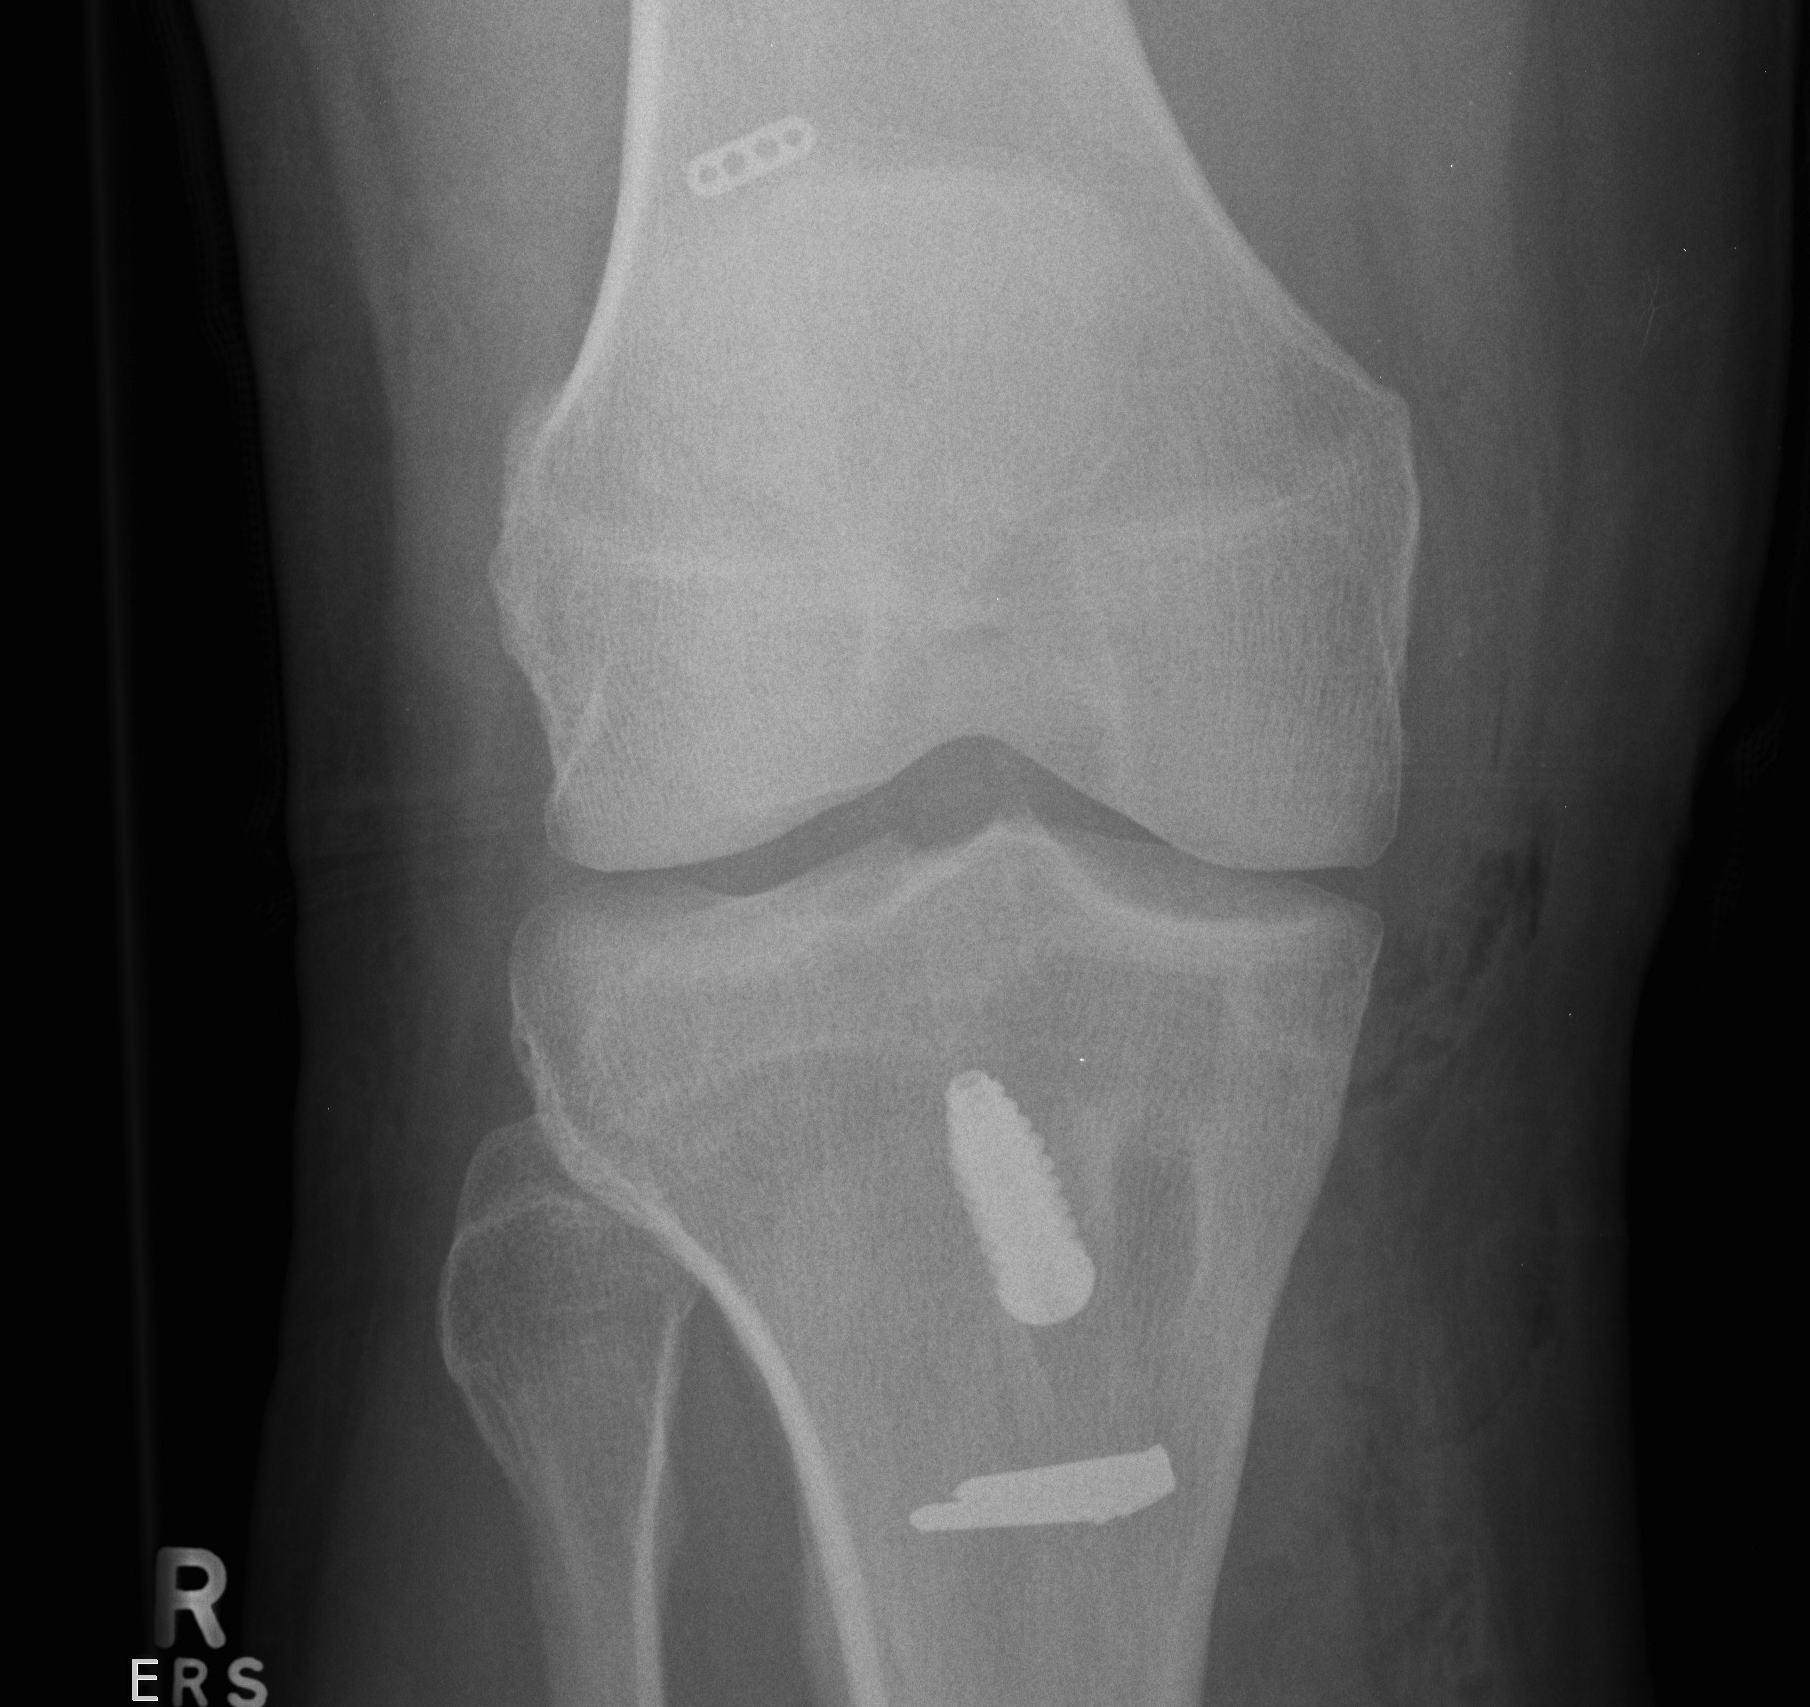

Tibial fixation

Place beath wire and pass RCI screw anteriorly

- usually 8 or 9 mm for men and women

- the tibial bone is soft

- will usually take a 25 mm screw / up to 35 mm

- +/- supplemental post / screw / staple